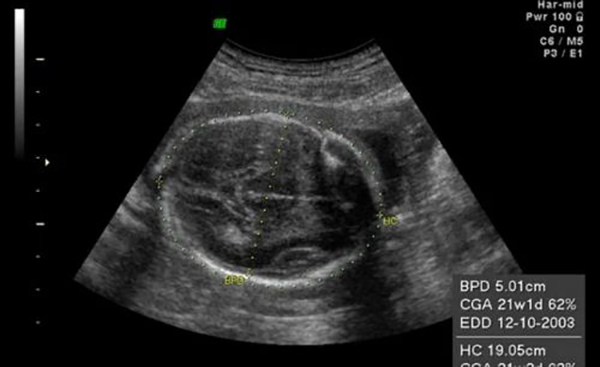

Đường kính lưỡng đỉnh (thông số BPD) là kích thước đo được tại mặt cắt lớn nhất của vùng từ trán ra sau gáy của thai nhi. Một cách đơn giản, đây chính là đường kính phần đầu thai nhi. Phương pháp siêu âm được áp dụng để xác định đường kính lưỡng đỉnh thai.

Khi thai bước vào tuần thứ 13 trở đi, mẹ bầu có thể siêu âm để biết các chỉ số đường kính lưỡng đỉnh, chi vi đầu, chiều dài xương,…của thai nhi. Trong suốt thai kỳ, đường kính lưỡng đỉnh thai thay đổi rất nhanh. Đường kính lưỡng đỉnh thai 37 tuần là một chỉ số quan trọng biểu hiện tình trạng thai nhi ở giai đoạn chuẩn bị chào đời.

Đường kính lưỡng đỉnh thai cùng với các chỉ số khác là căn cứ để xác định trọng lượng, tuổi thai và tốc độ phát triển hiện tại của thai nhi. Khi siêu âm và nhận thấy đường kính lưỡng đỉnh không đạt chuẩn, bác sĩ có thể yêu cầu tiến hành các xét nghiệm khác để kiểm tra dấu hiệu bất thường ở thai nhi. Chỉ số đường kính lưỡng đỉnh phải trong một giới hạn nhất định. Nếu đường kính lớn đồng nghĩa với phần đầu của thai lớn sẽ gây khó khăn cho mẹ bầu khi sinh.